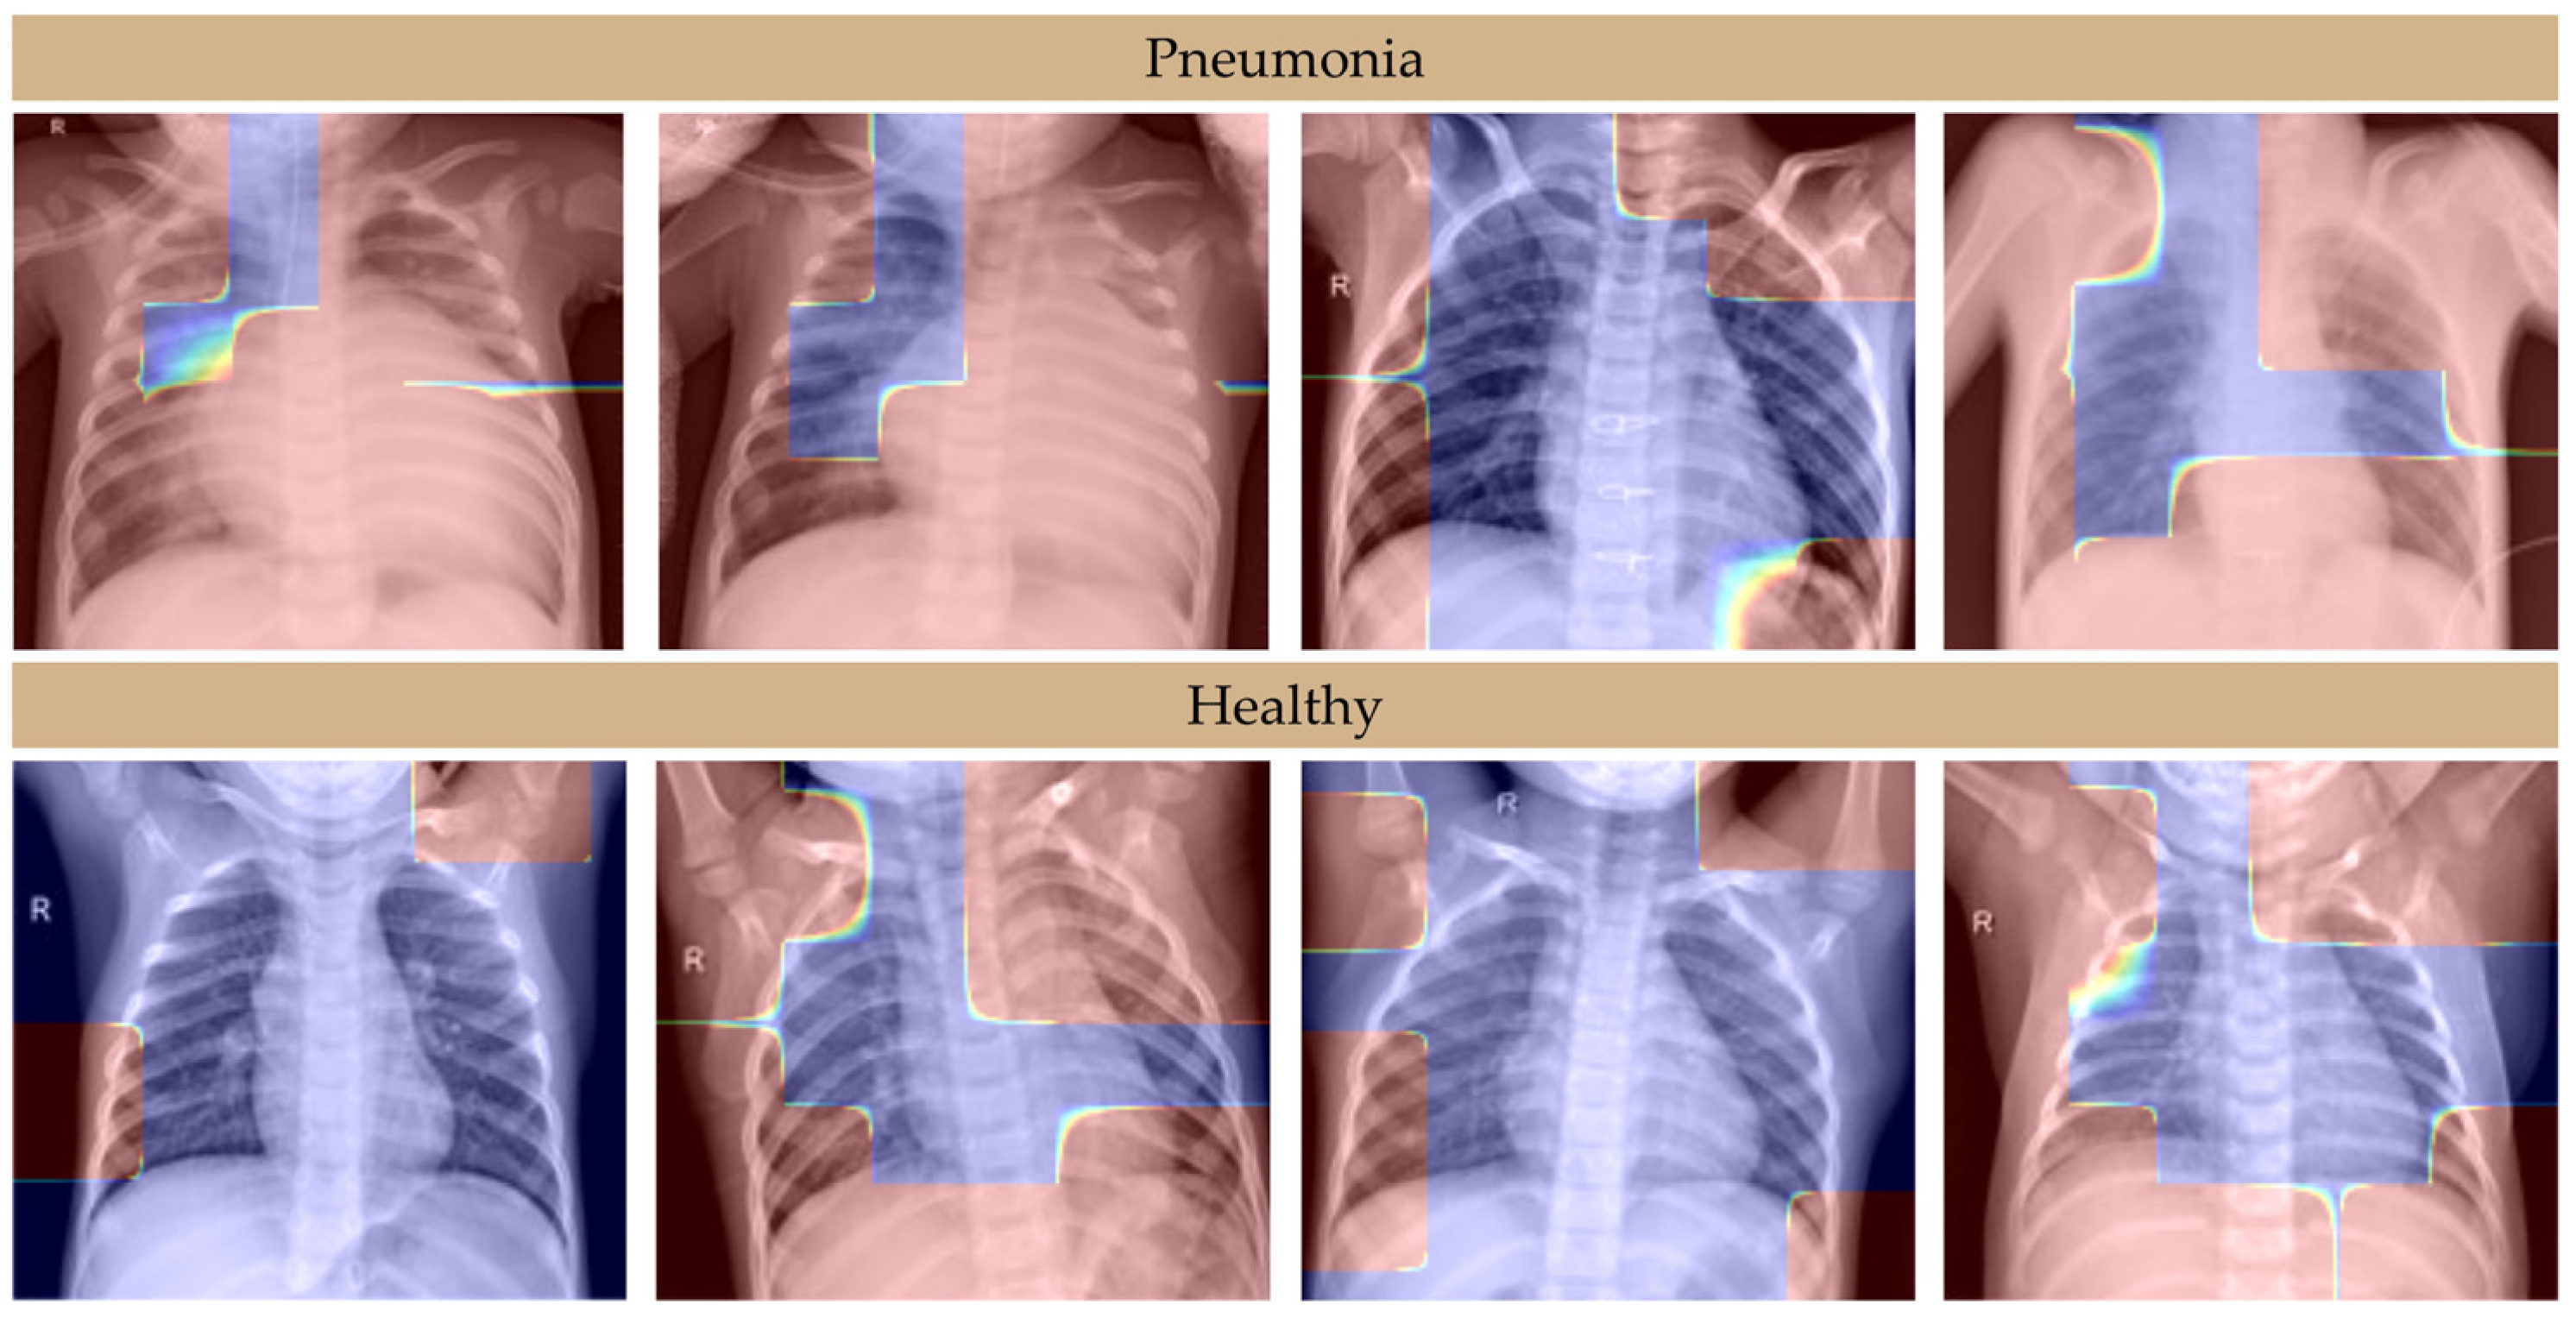

We used the publicly available Chest X-ray Images (Pneumonia) dataset [30] for our experiments, which includes X-ray images of pediatric patients aged one to five years from Guangzhou Women and Children’s Medical Center. The dataset contains 5856 images, categorized into two groups: pneumonia (4273 images) and healthy (1583 images) [30]. All chest radiographs were initially screened for quality control, and low-quality or unreadable scans were removed prior to analysis. Diagnoses for the images were graded by two expert physicians, with a third expert verifying the evaluation set to minimize grading errors and ensure the reliability of the dataset [30]. Samples of used images are shown in Figure 2. To ensure a balanced evaluation, we performed a stratified random split of the dataset into training and validation subsets in an 80:20 ratio, preserving the class distribution. Due to computational resource constraints and the large dataset size, we opted for a single 80:20 split instead of k-fold cross-validation, which would have significantly increased training time without providing proportional benefits in this context. Although we did not apply explicit measures such as class weighting or oversampling to address the class imbalance, the CNN inherently adapts to the data distribution through its training process. Additionally, data augmentation techniques, including rotation, shifting, zooming, and horizontal flipping, were applied during preprocessing to increase dataset variability and improve model generalization. All images were resized to 224 × 224 pixels.

Figure 2. Samples of the pneumonia and healthy chest X-ray images used in this study.